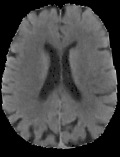

Accurate infarct segmentation in non-contrast CT (NCCT) images is a crucial step toward computer-aided acute ischemic stroke (AIS) assessment. In clinical practice, bilateral symmetric comparison of brain hemispheres is usually used to locate pathological abnormalities. Recent research has explored asymmetries to assist with AIS segmentation. However, most previous symmetry-based work mixed different types of asymmetries when evaluating their contribution to AIS. In this paper, we propose a novel Asymmetry Disentanglement Network (ADN) to automatically separate pathological asymmetries and intrinsic anatomical asymmetries in NCCTs for more effective and interpretable AIS segmentation. ADN first performs asymmetry disentanglement based on input NCCTs, which produces different types of 3D asymmetry maps. Then a synthetic, intrinsic-asymmetry-compensated and pathology-asymmetry-salient NCCT volume is generated and later used as input to a segmentation network. The training of ADN incorporates domain knowledge and adopts a tissue-type aware regularization loss function to encourage clinically-meaningful pathological asymmetry extraction. Coupled with an unsupervised 3D transformation network, ADN achieves state-of-the-art AIS segmentation performance on a public NCCT dataset. In addition to the superior performance, we believe the learned clinically-interpretable asymmetry maps can also provide insights towards a better understanding of AIS assessment. Our code is available at https://github.com/nihaomiao/MICCAI22_ADN.